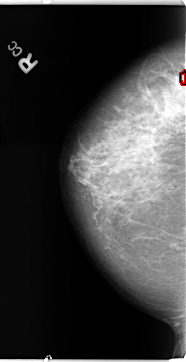

B_3116_1.RIGHT_MLO

RIGHT_MLO LINES 4776 PIXELS_PER_LINE 2768 BITS_PER_PIXEL 12 RESOLUTION 50 OVERLAY

FILE: B_3116_1.RIGHT_MLO.OVERLAY

TOTAL_ABNORMALITIES 1

ABNORMALITY 1

LESION_TYPE MASS SHAPE OVAL MARGINS CIRCUMSCRIBED-OBSCURED

ASSESSMENT 4

SUBTLETY 4

PATHOLOGY BENIGN

TOTAL_OUTLINES 1

BOUNDARY